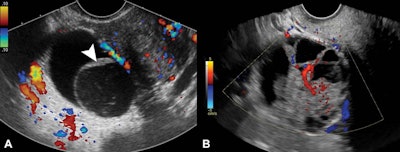

A multi-institutional research team found that pelvic ultrasound can be a good predictor of whether adnexal lesions will become ovarian cancer. (A) Transverse color Doppler image of right adnexa shows what's consistent with a nonclassic lesion without blood flow. This multilocular cystic lesion shows smooth septation and no Doppler flow. (B) Transverse color Doppler image of right adnexa is compatible with a nonclassic lesion with blood flow. It shows a multilocular cystic lesion with solid component and internal Doppler flow. Image courtesy of RSNA.

A multi-institutional research team found that pelvic ultrasound can be a good predictor of whether adnexal lesions will become ovarian cancer. (A) Transverse color Doppler image of right adnexa shows what's consistent with a nonclassic lesion without blood flow. This multilocular cystic lesion shows smooth septation and no Doppler flow. (B) Transverse color Doppler image of right adnexa is compatible with a nonclassic lesion with blood flow. It shows a multilocular cystic lesion with solid component and internal Doppler flow. Image courtesy of RSNA.Women with average risk for ovarian cancer had a 1% frequency of malignancy in lesions with classic ultrasound features showing simple cysts, hemorrhagic cysts, endometriomas, or dermoids. Lesions that had a solid component with blood flow had a 32% (33 of 103) frequency of malignancy. This was higher in women older than 60, with a frequency of 50% (10 of 20).